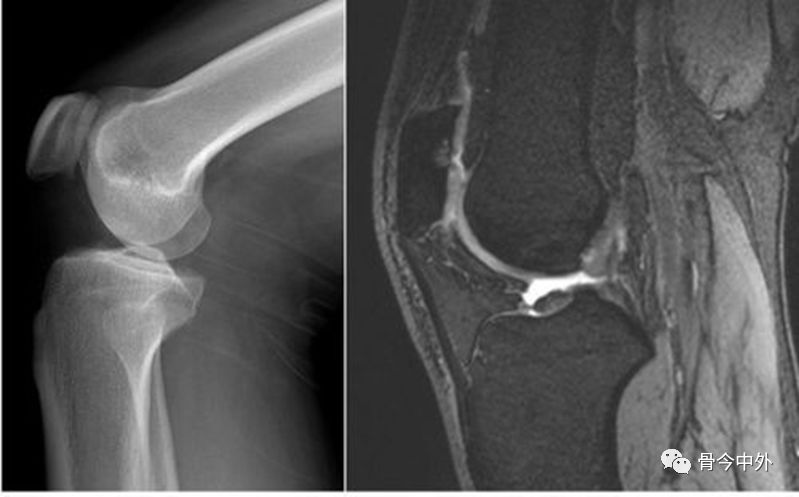

膝关节穿刺术常用于检查关节腔内积液的性质,或抽液后向关节腔内注药。膝关节腔内积液,需行关节穿刺抽液检查或引流,或注射药物进行治疗。关节腔内注射空气或造影剂,行关节造影术,以了解关节软骨或骨端的变化。

膝关节囊、韧带和肌腱附着点,神经分布较为密集。许多神经分支深入到膝关节腔内的软骨、滑膜和软骨下血管。许多无髓鞘神经未梢感受器还与血管走行共同分布于关节囊、滑膜和关节脂肪垫。